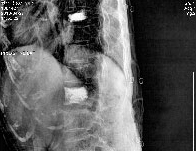

제 4/5 경추간 추간판 탈출증으로 수술 -

제 4/5 경추간 추간판 탈출증으로 수술